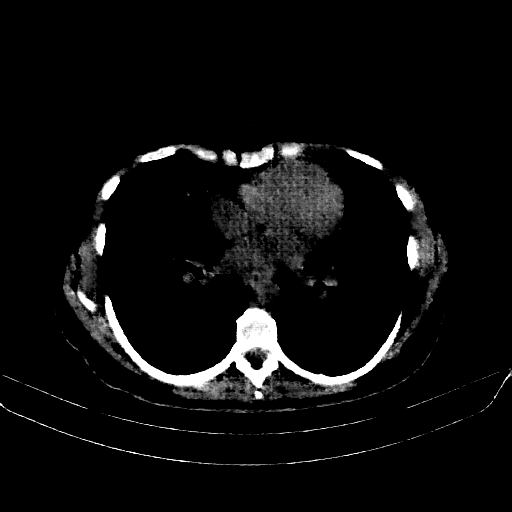

Image Grid

4Γ—3 grid: Rows show different image types (Original NATIVE, Reconstructed NATIVE, Original VENOUS, Generated VENOUS), Columns show windowing techniques (No Window, Lung Window, Mediastinum Window)

Targeted Slice 70 - Mediastinum Window Analysis (Generated vs Real Venous)

0.709

Mediastinum SSIM

83.3

Mediastinum RMSE

34.9

Mediastinum MAE

Mediastinum window (WL 40, WW 400 β†’ Low βˆ’160, High +240)

Generated VENOUS CT scan (A→B translation)